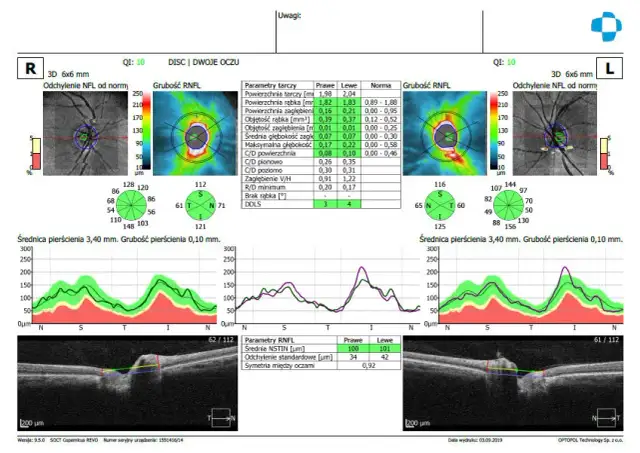

Badanie OCT: Co to jest, jak przebiega i czy wykryje jaskrę?

Badanie OCT: dowiedz się, czym jest ta precyzyjna tomografia oka, jak przebiega, co diagnozuje (jaskra, AMD) i ile kosztuje. Sprawdź nasz przewodnik!